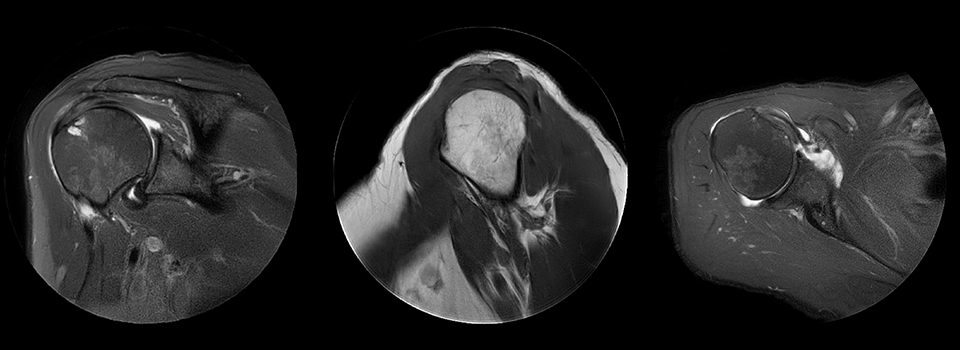

Shoulder with MultiVane motion reduction

MultiVane was used for motion reduction in this shoulder examination, providing excellent detail that is not obscured by motion artifacts, as happens quite commonly when no proper motion reduction method is available. Images from Ingenia Ambition.

Cor T2W fatsat

Scan time 3:06 min

Voxels 0.5 x 0.5 x 3 mm, recon 0.4 x 0.4

Sag T1W

Scan time 4:10 min

Ax PD fatsat

Scan time 4:17 min